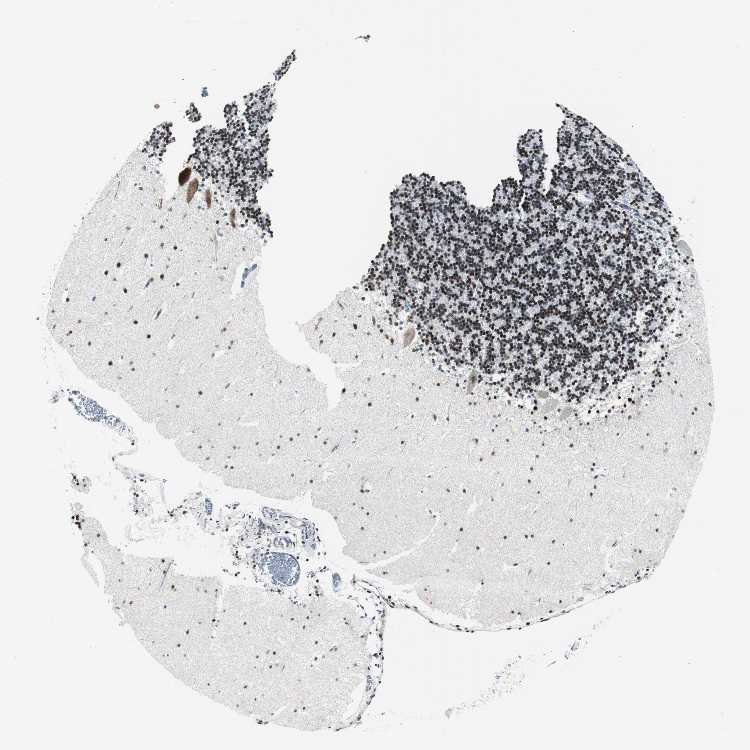

CEREBELLUM - Antibody stainingi

Antibody staining in the annotated cell types in the current human tissue is reported as not detected, low, medium, or high, based on conventional immunohistochemistry profiling in selected tissues. This score is based on the combination of the staining intensity and fraction of stained cells.

Each image is clickable and will lead to virtual microscopy that enables deeper exploration of all samples and also displays staining intensity scores, fraction scores and subcellular localization as well as patient and tissue information for each sample.

Antibody HPA005544Antibody CAB004508

Purkinje cells HighLow

Cells in granular layer -High

Cells in molecular layer LowMedium